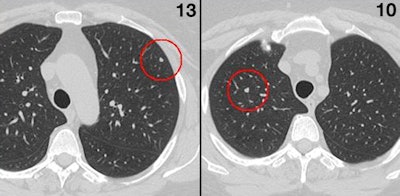

The study included 155 nodules: 74 solid, 22 part solid, and 59 ground-glass opacities, with a 5.5-mm average diameter. Four readers looked at various combinations of thick (5-mm) and thin (1-mm) slices.

All reading paradigms that involved CAD reading thin sections alone were better (71% to 95%) than the reader working without CAD (sensitivities 57% to 81%), though, predictably, CAD working alone had a higher false-positive rate of about three per case.

The reading paradigm with the highest sensitivity (82% to 97% depending on nodule type) occurred in CAD when both the reader and CAD analyzed thin sections. The worst performance (sensitivities of 40% to 77%) occurred when the reader was asked to assess marks that CAD had detected on thick sections. This is because it's harder for the reader to discern whether CAD markings from thick sections are true-positive or not, Rubin said.

But even though the CAD thin/reader thin paradigm delivered the highest sensitivity, CAD thin/reader thick (sensitivities 77% to 94%) was actually the optimal combination: It nearly equaled the sensitivities of CAD thin/reader thin (82% to 97%) but produced less uncertainty for the reader, leading to fewer false positives.

Consequently, the authors reported that false positives rose from 0.64 to 0.90 per case (compared with no CAD) when CAD and the reader both examined thin sections (p < 0.001), but false positives didn't increase when CAD examined thin sections and the reader looked at thick.

"When the reader is presented with thick sections, they have many fewer sections to look at. It's a more efficient paradigm, and the reduction in sensitivity isn't that great," Rubin said. Therefore, the most effective reading paradigm was CAD thin/reader thick, "allowing the radiologist to comfortably and confidently read thick sections, and then look at CAD's premarkings and evaluate the thin sections to validate that and perform at a high level -- almost as high as if the radiologist read exclusively thin sections."